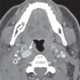

Enlarged lateral retropharyngeal lymph node